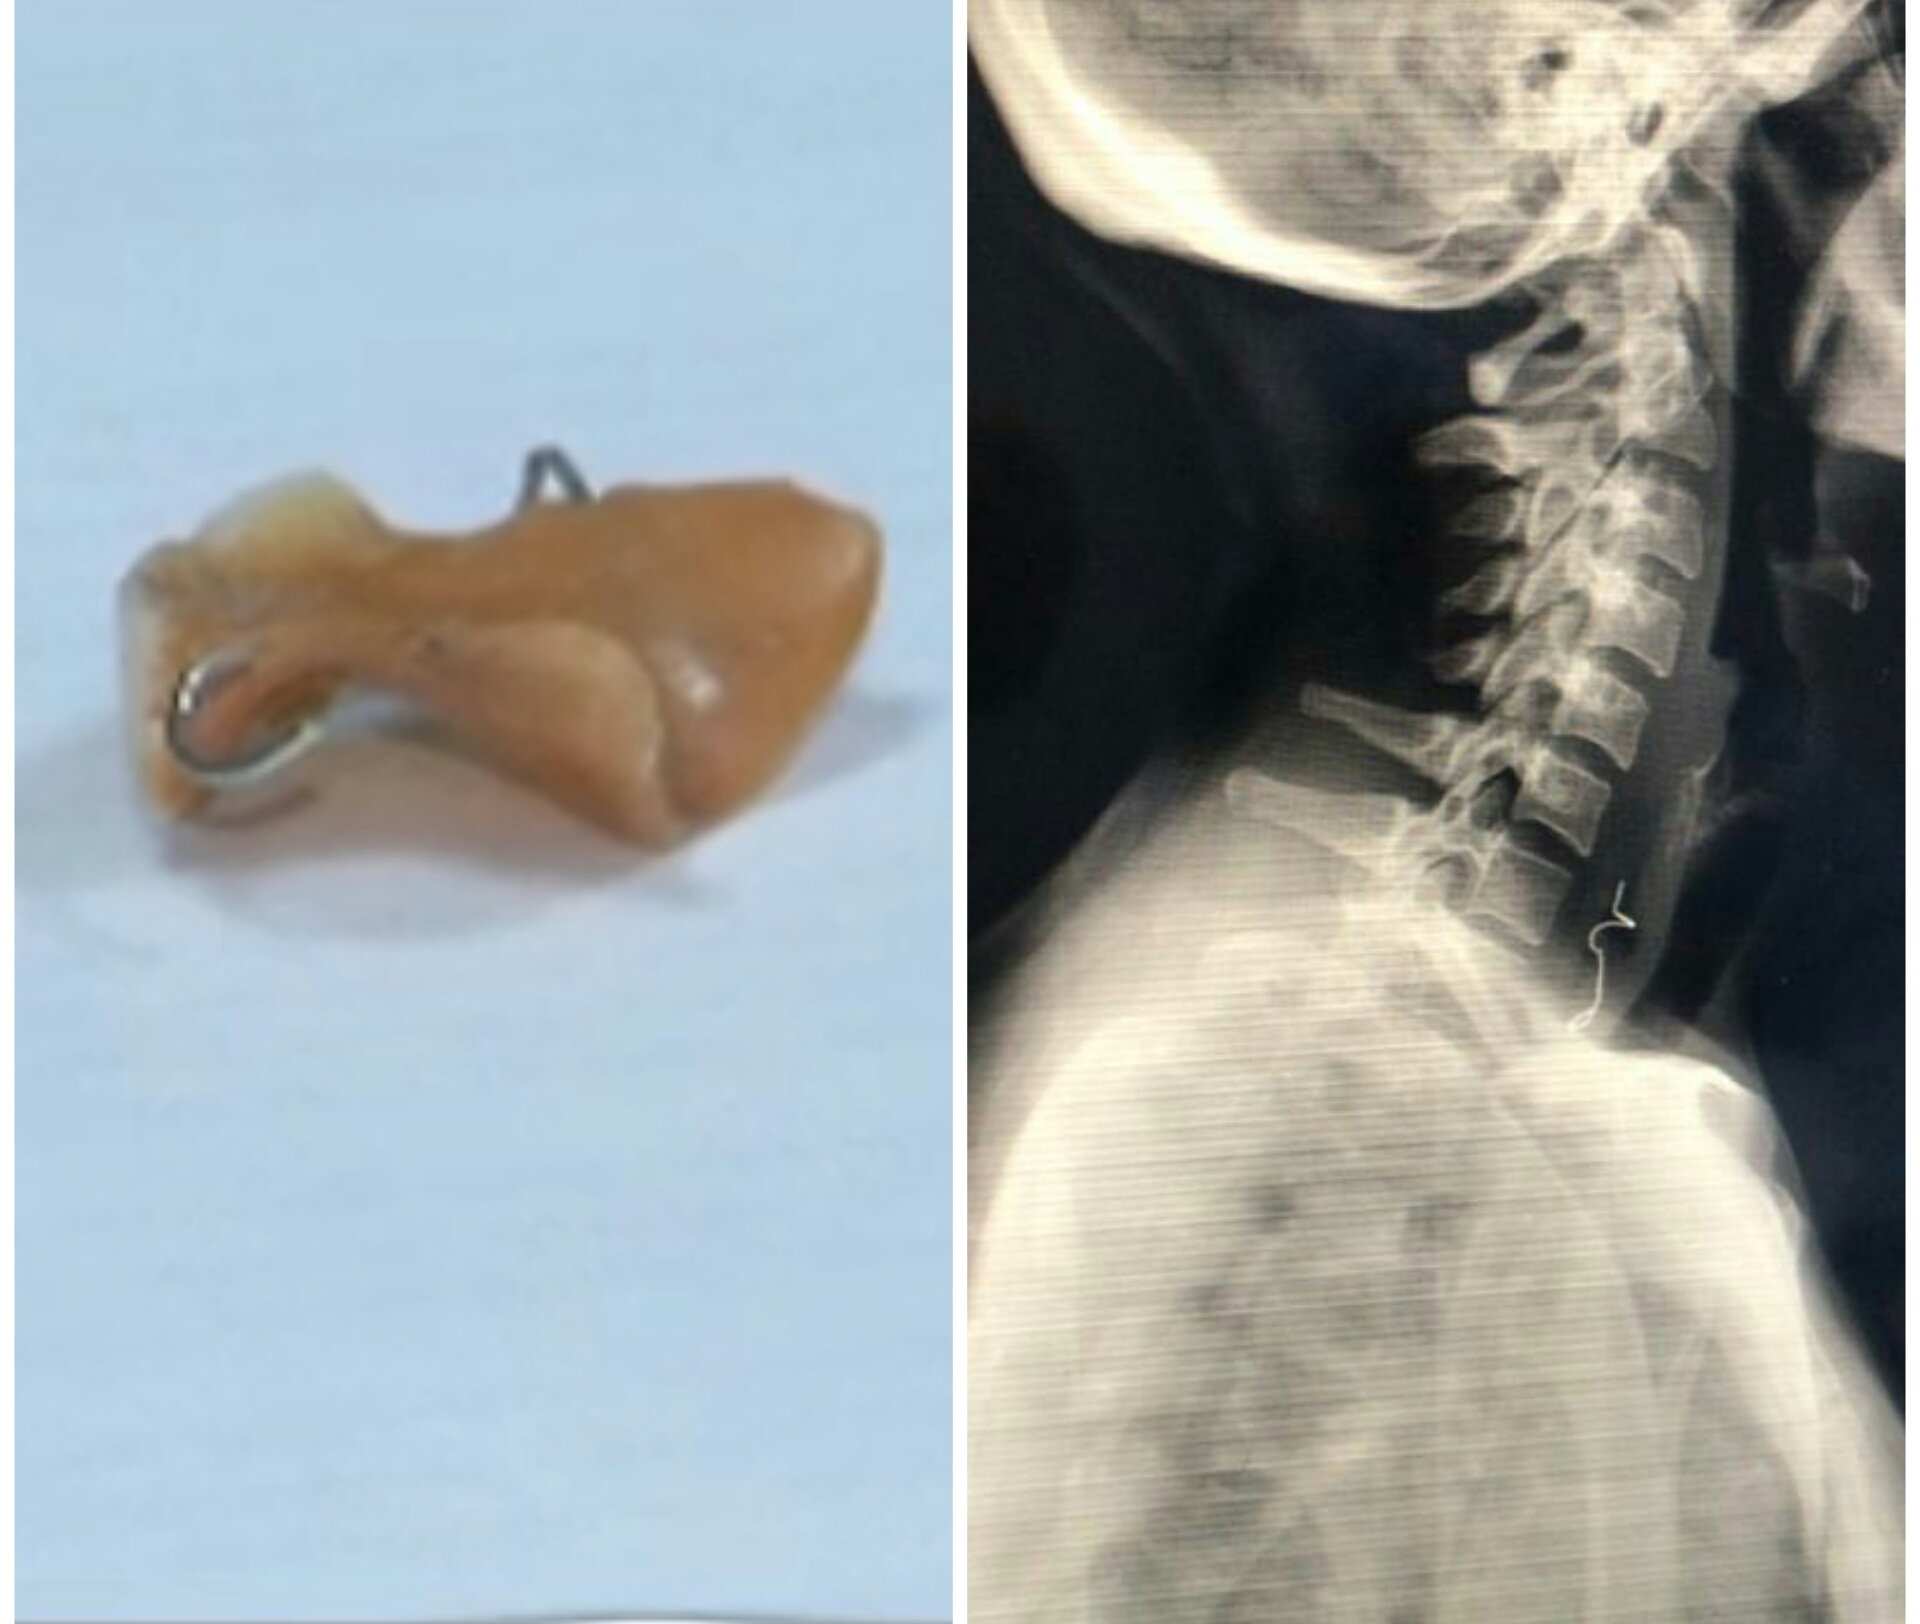

Santo Domingo, RD.- Tras tener alojado en el esófago su prótesis dental, una mujer de 43 años fue intervenida quirúrgicamente por cirujanos del hospital docente universitario doctor Francisco E. Moscoso Puello.

Durante la cirugía se desbridó un 10% de tejido desvitalizado del esófago secundario, debido a que la prótesis dental utilizó músculos del cuello como colgajos.

«La única salida para salvar la vida de la mujer era la cirugía, esto a pesar de todos los parámetros en contra, donde las complicaciones post-quirúrgicas por fístulas, infección, sepsis y muerte son de alto porcentaje», manifestó el doctor Rosario.